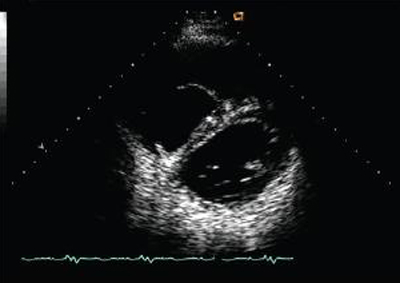

Visualização ecocardiográfica em eixo curto em um paciente com regurgitação pulmonar após reparo de tetralogia de Fallot. O paciente tem ventrículo direito restritivo e a visualização ecocardiográfica em eixo curto revela ventrículo direito grande

De: Chaturvedi RR, Redington AN. Heart. 2007 Jul;93(7):880-9; usado com permissão